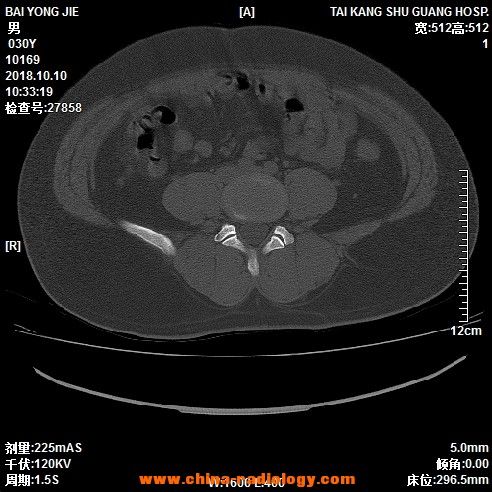

骶椎隐裂ct片图解图片

骶椎隐裂ct片图解图片,骶椎隐裂

[已会诊] 第1骶椎隐裂?